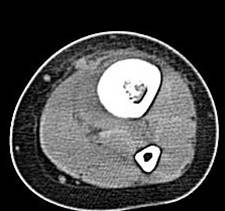

男孩,5岁,左小腿疼痛,肿胀,活动受限20天。

左胫骨中下段见一长卵圆形骨质破坏区,走形方向与胫骨长轴一致,边缘轻度硬化,内后侧骨皮质破坏,伴明显骨膜增生,破坏区内呈软组织密度。未见明显软组织肿块。

左胫骨中下段见一不规则虫蚀样骨破坏,走形方向与胫骨长轴一致,边缘轻度硬化,伴明显骨膜增生,ct见破坏区内见磨玻璃样密度,其旁软组织钟胀,内见不规则钙化。

左胫骨中下段见一不规则虫蚀样骨破坏,走形方向与胫骨长轴一致,边缘轻度硬化,伴明显规则的骨膜增生,ct见破坏区内见磨玻璃样密度,其旁软组织钟胀,内见不规则钙化。

病史资料不完善,根据年龄、部位、及影像学表现,主要表现胫骨骨干囊性骨质破坏,骨皮质受累,局部骨膜反应,未见骨膜破坏及瘤骨,未见放射状骨针。 首先要考虑胫骨转移瘤,建议进一步检查,除外视网膜母细胞瘤,神经母细胞瘤,肾母细胞瘤,肾上腺等恶性肿瘤骨转移。排除转移瘤后考虑嗜酸性肉芽肿可能性大,患者年龄5岁,尤文氏瘤不太考虑,骨肉瘤也不太符合,骨髓炎待排,影像表现不太支持。建议进一步检查,除外原发恶性肿瘤胫骨转移后,考虑嗜酸性肉芽肿。必要时穿刺活检。